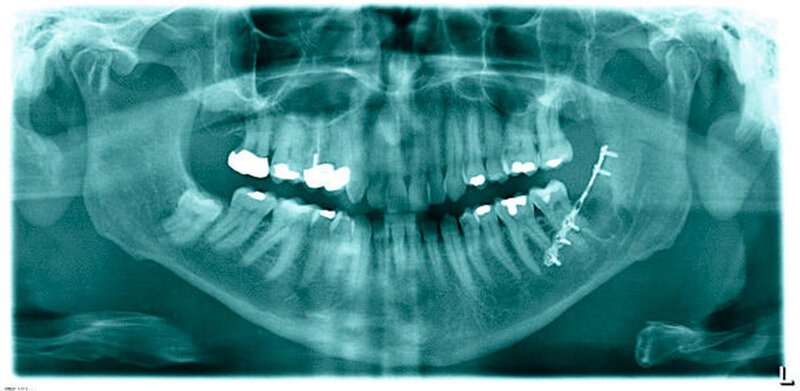

Bei typischer Anamnese mit lautem Knacken beim Zubeißen lag der Verdacht einer Fraktur des Unterkiefers links vor, so dass zur weiterführenden Diagnostik eine digitale Volumentomografie des Kieferwinkels links durchgeführt wurde (Abbildungen 2 und 3).

In dieser kann man die fissurale Fraktur der vestibulären Lamelle erkennen, die bei Zustand nach Osteotomie der eingekürzten vestibulären Lamelle vom tiefsten Punkt derselben nach caudal distal verläuft. Ebenfalls zu erkennen ist die Mitbeteiligung der vestibulär gelegenen Spongiosa. Die medialen Anteile der Spongiosa und die linguale Lamelle des Unterkiefers waren von der Fraktur nicht affektiert.

Zur Vermeidung einer kompletten Fraktur und einer potenziellen Dislokation der Unterkieferanteile bei erneutem Insult wurde in Lokalanästhesie eine Miniplattenosteosynthese zur Stabilisierung durchgeführt. Die Platte wird prospektiv in einem halben Jahr wieder entfernt.

Im vorliegenden Fall gelang mit der digitalen Volumentomografie der Nachweis der Fraktur, so dass man sich hier entschlossen hat, die Fraktur mittels Miniplattenosteosynthese zu versorgen.